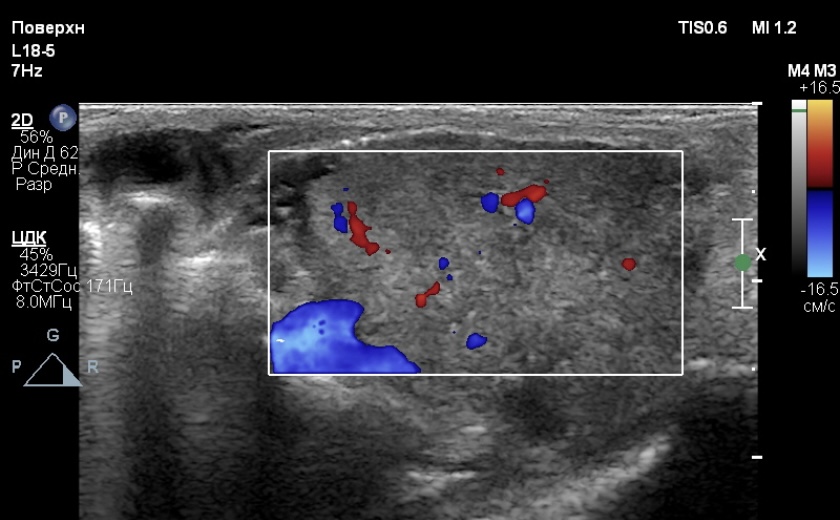

Животному были выполнены ультразвуковое исследование мягких тканей шеи, магнитно-резонансная томография области головы и шеи с контрастным усилением.Результаты УЗИ. В просвете ротоглотки было выявлено гетерогенное, преимущественно изоэхогенное образование с гипоэхогенными включениями неправильной формы, нечеткими контурами, размерами 15×16 мм (фото 2, 3).